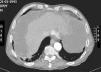

A 70-year-old man with significant past medical history of hypertension, atrial fibrillation and cerebral vascular disease was admitted for anorexia, weight loss (10kg) and increased abdominal girth for the past 3 months. On examination, a voluminous ascites was noted, with no signs of chronic liver disease. Laboratory studies showed an isolated elevation of serum inflammatory markers (C-reactive protein and erythrocyte sedimentation rate). Abdominal ultrasound (US) and computed tomography (CT) were performed and revealed CT low-attenuation heterogeneous ascites that scalloped the margins of the liver and spleen (Fig. 1). Diagnostic paracentesis revealed thick gelatinous ascitic fluid, rich in mucin on cytology examination (Figs. 2 and 3). Ascitic fluid cell count was not possible due to high viscosity and cultures were negative.

The radiologic and cytotogic findings were crucial to support the diagnosis of pseudomyxoma peritonei (PMP). Despite being proposed for surgery, there was a rapid clinical deterioration and the patient died 11 weeks after the diagnosis.

PMP is a rare and intractable clinical syndrome, with an estimated incidence of 1–2 per million per year. It is characterized by copious amounts of mucinous ascites and mucinous peritoneal implants, leading to progressive obliteration of the peritoneal cavity and intestinal obstruction. The most common sites of origin are tumors of the appendix and ovary and in up to 5% of the patients the origin remains unknown. Despite being a rare cause of ascites, with approximately one hundred cases reported worldwide, PMP must be considered in the differential diagnosis of ascites, particularly if gelatinous. Imaging is key to the initial diagnosis, revealing typical findings on US, CT and magnetic resonance imaging such as heterogeneous ascites scalloping the visceral surface of the liver and spleen. Diagnostic confirmation is made by ascitic fluid cytology showing abundant extracellular mucus. Treatment is controversial and the most satisfactory and effective approach is a combination modality of cytoreductive surgery and intraoperative chemotherapy.1–3